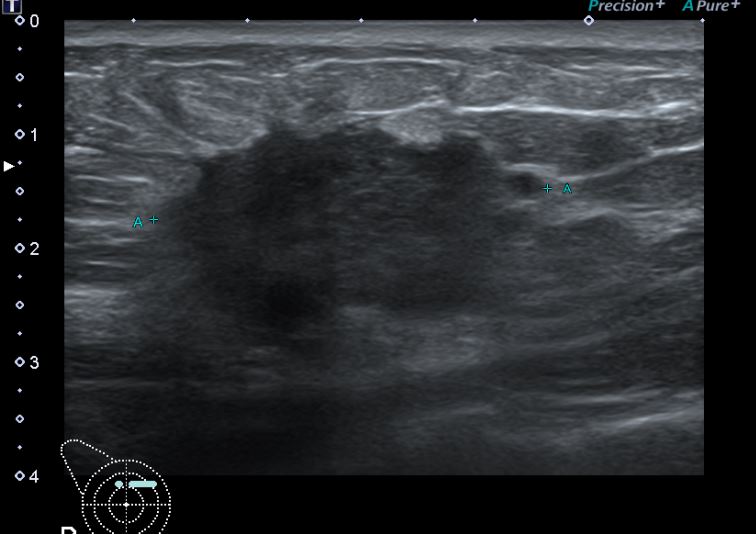

상기환자 외부검사상 이상소견으로 내원하신 50대 후반 여성분으로

우측 조직검사 시행해 침윤성 유방암으로 진단되었습니다